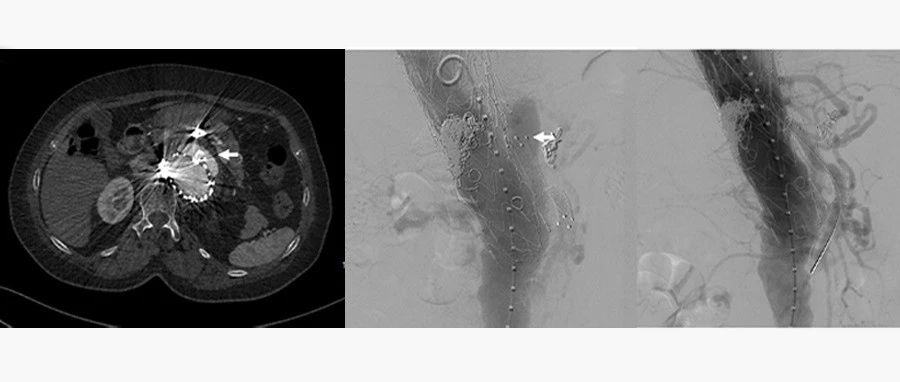

2022 CEC 手术精选 | 寇镭:Shockwave冲击波导管治疗髂动脉严重钙化病变